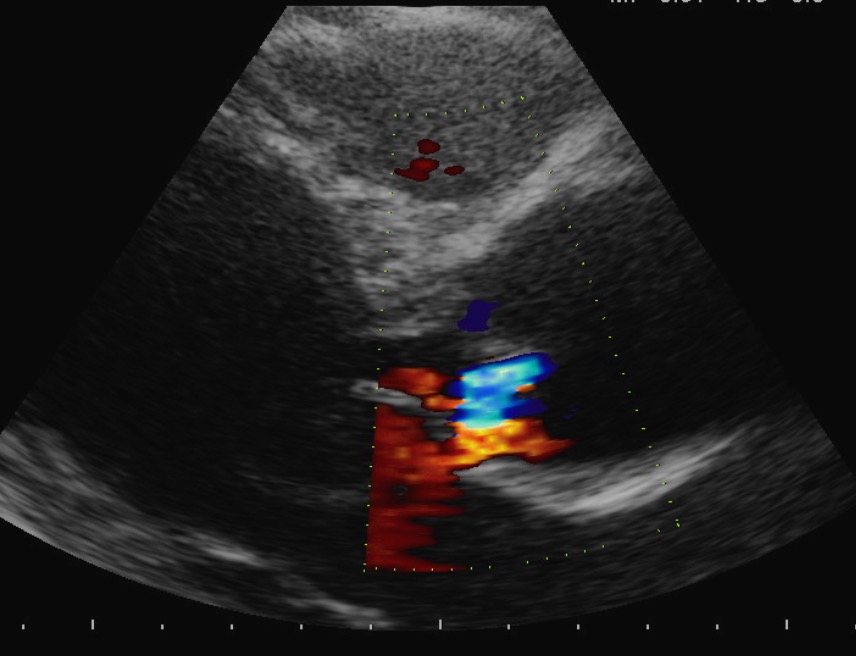

Color Doppler come va impostato

Autore:

Eleonora Zenoni